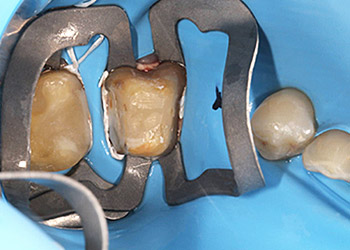

Heutzutage werden, um den Kofferdamm am Zahn zu befestigen, sogenannte Kofferdam-Klammern verwendet. Diese umfassen den Zahn ringförmig und sind in allen nur denkbaren Formen erhältlich. Für die Lochung werden heute keine heißen Instrumente, sondern Lochzangen verwendet, je nach Größe des Zahnes, um Löcher für die Zähne in das Gummituch zu stanzen.

Häufig findet also der Kofferdam seine Anwendung in der Zahnerhaltung, bei Composite-Restaurationen, endodontischen Behandlungen oder Präparationen mit späteren adhäsiven Befestigungen. Denn gerade bei aufwendigen Wurzelkanalbehandlungen, wo der Zahn desinfiziert und von innen gereinigt wird, sollte es vermieden werden erneut Bakterien, z.B. aus dem Speichel in das Wurzelkanalsystem zu transportieren.